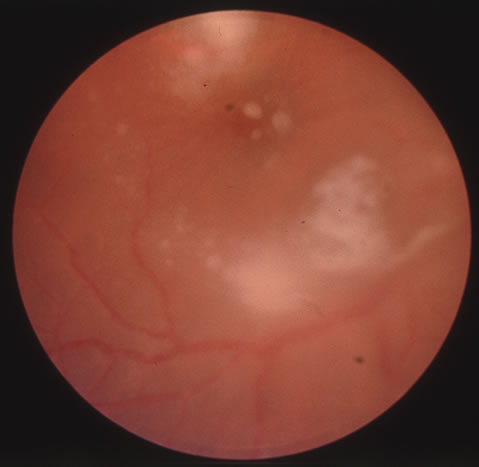

CMV retinitis is common in patients with AIDS. Perivascular granular white or yellowish infiltrates with hemorrhage are typical (Fig. 7). Minimal vitritis or anterior uveitis may be present. The posterior pole, including optic nerve, or peripheral retina may be involved. Optic neuritis may be retrobulbar. Resolution of retinal lesions reveals local retinal atrophy and pigment dispersion. Iridocyclitis may occur secondary to infection of ciliary processes. CMV retinitis in patients with AIDS is considered a poor prognostic sign in terms of life expectancy. Congenital CMV infection may also cause retinitis, as well as anterior uveitis, cataract, and optic atrophy. New foci of retinochoroiditis can develop in later years of congenital infection, and such infants require periodic reexamination as long as virus is shed in the urine.

Fig. 7. Cytomegalovirus retinitis in a patient with aquired immune deficiency syndrome (AIDS). Note the large area of retinal necrosis along with the perivascular distribution of the lesions.